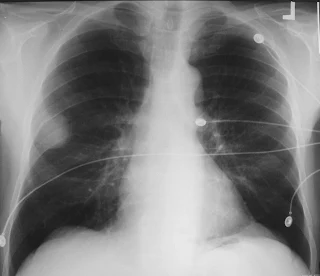

• X-ray : Coin shadow• Bronchoscopy : Biopsy (bleeding should be anticipated)